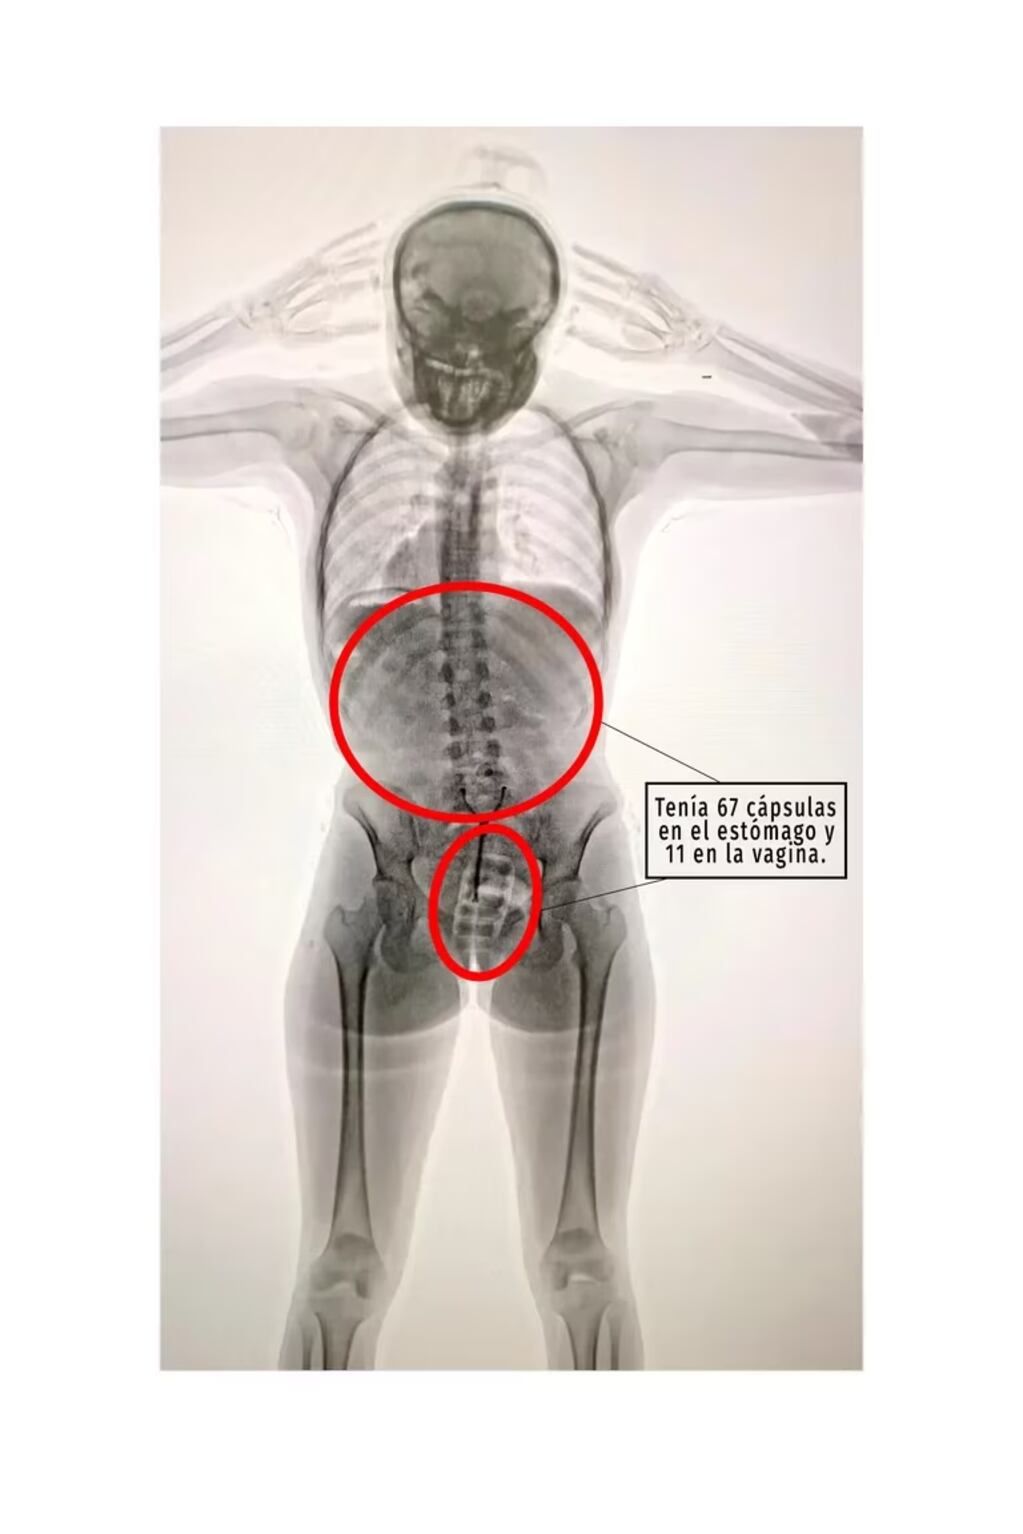

Una joven “mula” de 20 años fue detenida en el Aeropuerto Internacional de Ezeiza a punto de abordar un vuelo a España. Tras pasarla por el escáner notaron que tenía cápsulas dentro de su cuerpo, por lo que debió ser internada para su extracción: tenía guardadas 67 cápsulas de cocaína en el estómago y 11 en la vagina.

Según informaron fuentes judiciales, la muchacha debió quedar internada y fue allí que los médicos detectaron la presencia de las capsulas, de 10 gramos cada una, introducidas en la zona vaginal y en el sistema digestivo.

La joven detenida por droga en Ezeziza tenía cápsulas de cocaína en el estómago y en la vagina. - Gentileza / Infobae

Allí se descubrió que la joven había ingerido 78 cápsulas de 10 gramos de cocaína cada una y las llevaba dentro de su cuerpo, por lo que de inmediato quedó en calidad de detenida y fue trasladada al Hospital Zonal General de Agudos Doctor Alberto Antranik Eurnekian, donde quedó internada.

Una fuente judicial explicó a Télam que, en el centro asistencial, “los médicos detectaron la presencia de elementos extraños introducidos en la zona vaginal y en el sistema digestivo”, por lo que fue sometida a un tratamiento para la evacuación total de todas las cápsulas.